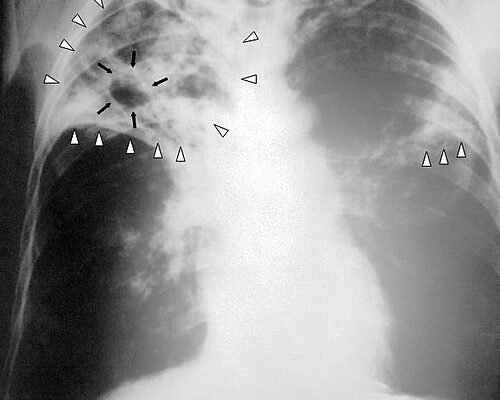

Діагностика: полювання на невидиме

Важливо звернути увагу, якого мастера потребує діагноз. Старанний лікар витончено вивчає таємні знаки, які проявляються у загадкових плямах на рентгенівському знімку.

- Рентгенографія — знайомимося з кольорами.